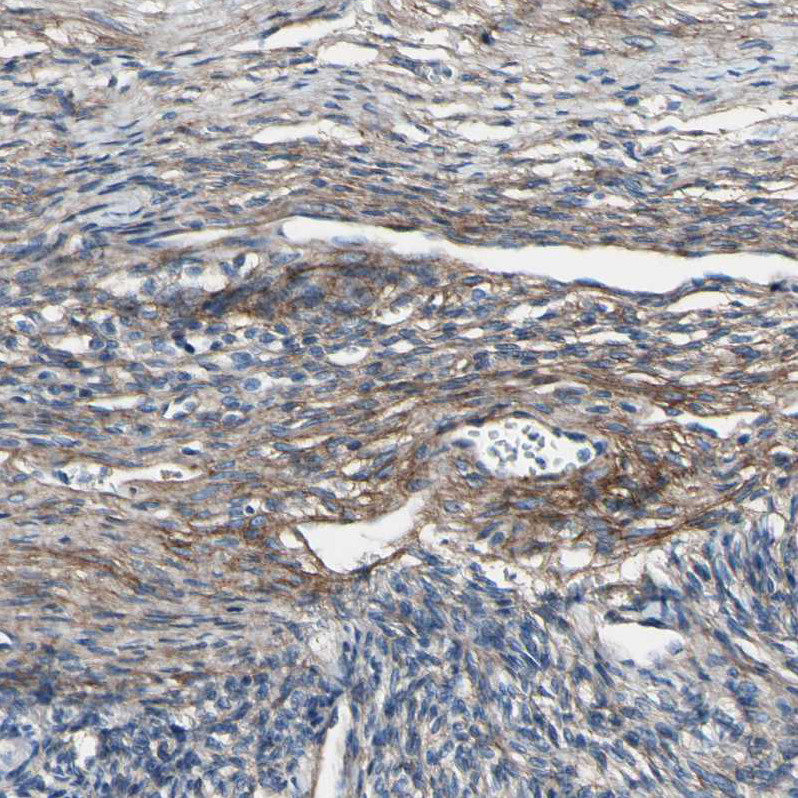

Immunohistochemical staining of human ovary shows moderate cytoplasmic positivity in connective tissues.